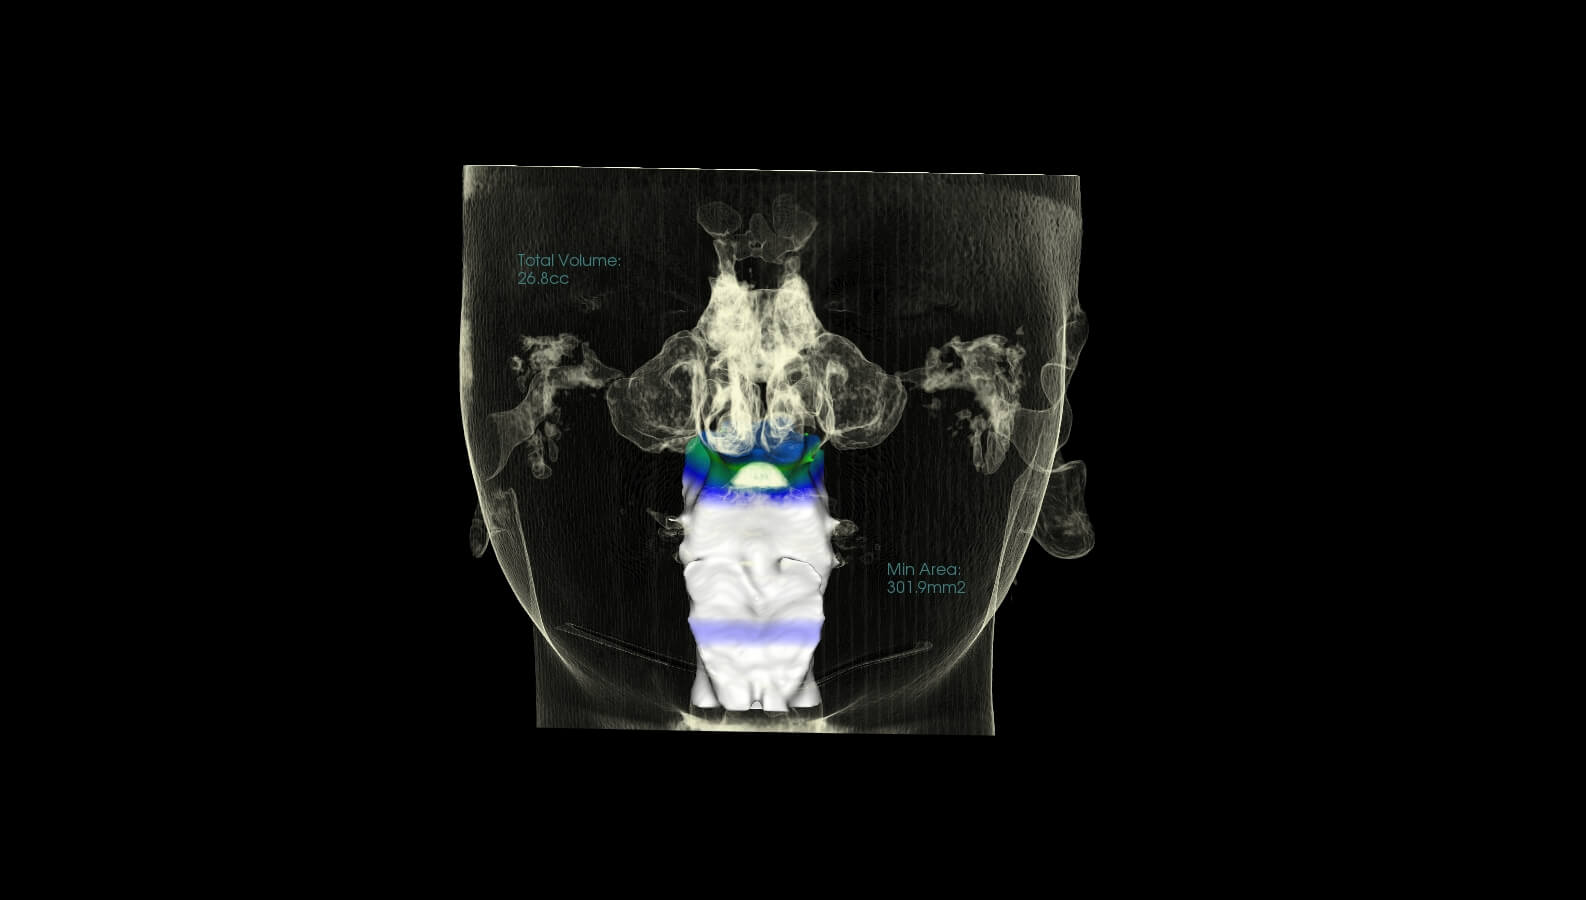

These are before and after CBCT images of patients treated at Marlo A. Miller, DDS. Both struggled with enlarged adenoids and tonsils. An adenotonsillectomy, or removal of the tonsils, was performed based on Dr. Miller and an ENT recommendation. This procedure alleviates airway restriction contributing to breathing/sleep issues and reduced overall health and wellness. Dr. Miller also did some minor Upper and Lower expansion. There is a Significant airway change in both patients, and both report sleeping better and feeling better overall.